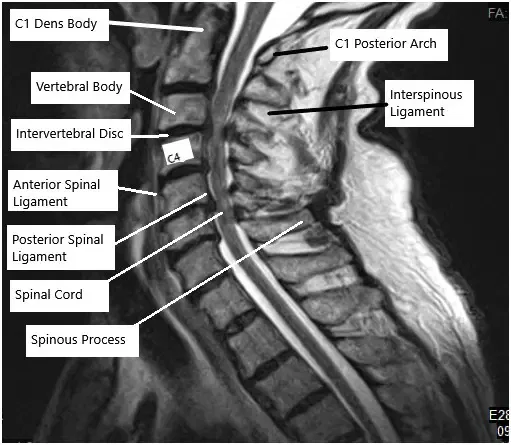

MRI of the cervical spine